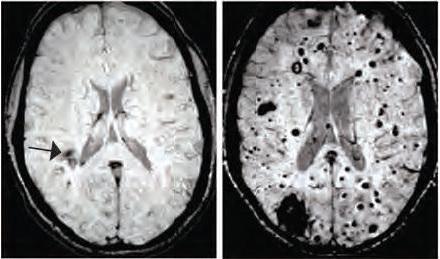

Ces dernières semaines, on ne compte plus les études qui documentent cet interface microbiote intestinal- cerveau. Une étude récente a apporté une démonstration imparable, chez la souris : greffer « du » microbiote humain d'un sujet atteint du syndrome du côlon irritable entraîne chez l'animal, non seulement le développement des mêmes symptômes intestinaux mais également un comportement qui reflète l'agitation et l'anxiété. La stimulation électromagnétique du cerveau peut également modifier la composition du microbiote intestinal. Enfin, des chercheurs de l'Université de York ont également montré que l'augmentation des niveaux alimentaires du neurotransmetteur inhibiteur, l'acide gamma-aminobutyrique (GABA), pouvait influencer les réponses neuronales aux stimuli sensoriels basiques. Enfin des chercheurs de l'Université de Californie – Los Angeles (UCLA) ont montré chez des patients atteints du syndrome du côlon irritable, l'association entre les microbes intestinaux et la structure du cerveau. Cette nouvelle étude suggère que le microbiote intestinal peut influencer la structure des vaisseaux sanguins du cerveau jusqu'au risque d'AVC ou d'épilepsie. Les malformations caverneuses cérébrales (MCC) – visuel de droite- sont des grappes de vaisseaux sanguins dilatés et à paroi mince qui peuvent entrainer des convulsions ou des accidents vasculaires cérébraux en cas de fuites de sang dans le tissu cérébral environnant.

Des changements dans le microbiote peuvent affecter la progression d'un trouble causé par une mutation génétique : cette équipe de scientifiques de l'Université de Pennsylvanie étudie ici les mécanismes qui provoquent la formation de ces hémangiomes chez des souris génétiquement modifiées et identifient ainsi un lien inattendu avec les bactéries intestinales. Lorsque certaines bactéries sont éliminées, le nombre de lésions diminue en effet considérablement. Les chercheurs ont développé des souris modèles de MCC, les ont transférées dans un nouvel environnement, et constatent que la formation des lésions est presque réduite à zéro - une variabilité dans la formation des lésions également observée chez les humains, où les patients porteurs de la même mutation génétique suivent souvent une évolution pathologique radicalement différente-. Cherchant à cerner la cause de cette variabilité soudaine, les scientifiques remarquent que les quelques souris qui continuent à former des lésions ont développé des abcès bactériens dans leur abdomen. Ces abcès contiennent des bactéries Gram négatives. Lorsque les chercheurs induisent volontairement ces infections bactériennes chez des animaux modèles de MCC, la moitié développe des lésions cérébrales significatives. Ces souris présentent également des abcès dans la rate, ce qui suggère que les bactéries intestinales sont entrées dans la circulation sanguine à partir du site d'abcès de départ. Il y a donc connexion ou propagation de l'intestin, à la rate et au cerveau via le flux sanguin. Et cette propagation entraine la formation de ces lésions vasculaires dans le cerveau.